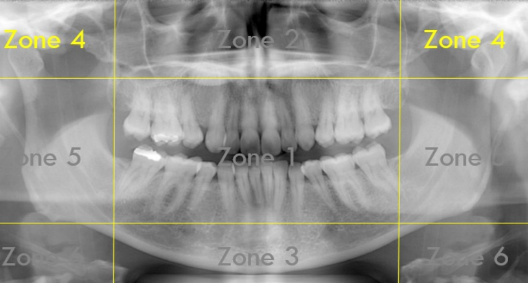

Identify The Zones.

Zone 1: Dentition

Zone 2: Nasal Cavity and Maxillary Sinuses

Zone 3: The Mandible

Zone 4: Temporomandibular Joints (TMJs)

Zone 5: Spine and Ramus

Zone 6: Hyoid Bone

What Zone Is This?

What do we see in Zone 5?